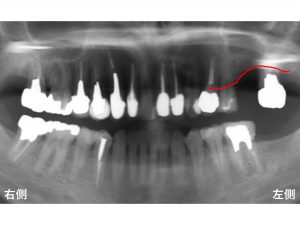

わかりやすいように骨吸収の状態を線でかいて見ます。

現在の骨吸収した状態が以下の赤線です。